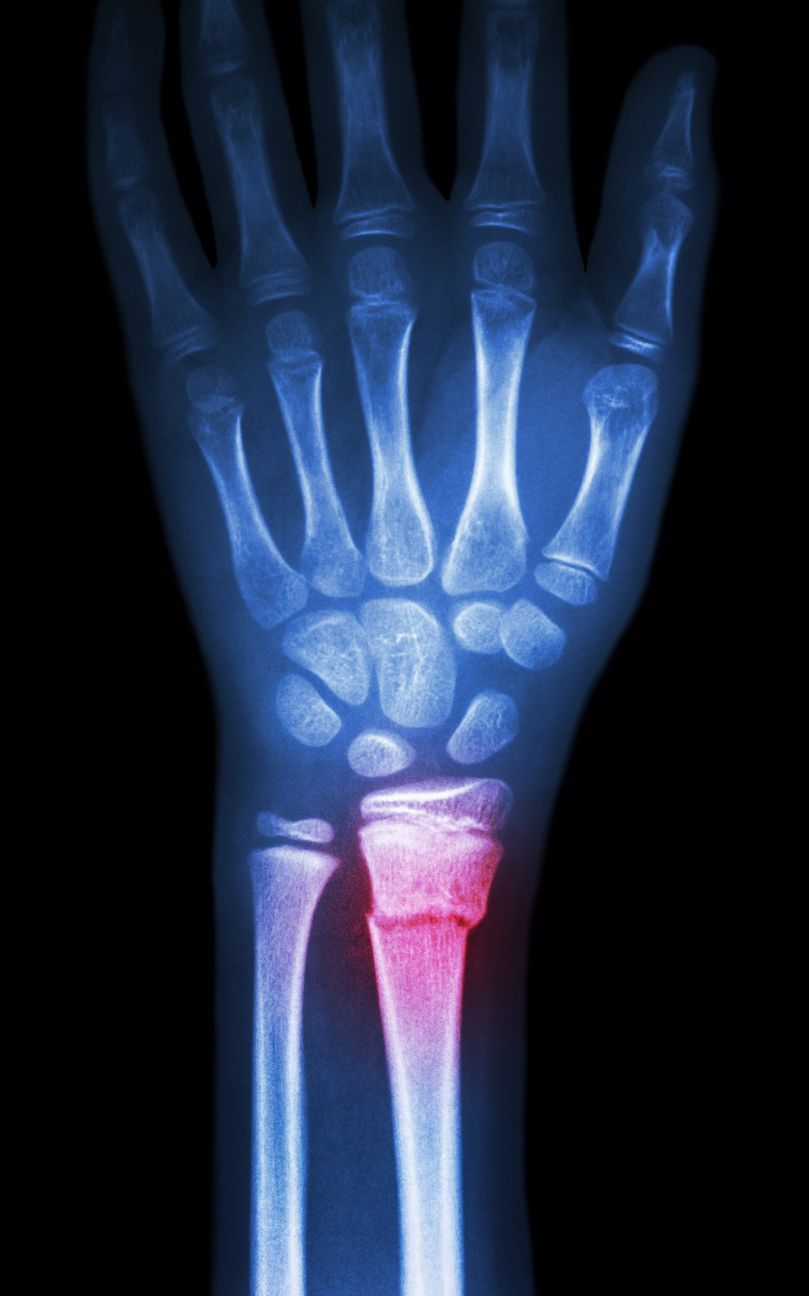

The carpal tunnel is formed by an osteofibrous wall which comprises of the flexor retinaculum which forms the superior boundary and the carpal bones which form the inferior border which provides passage for the wrist flexor and median nerve into the hand.